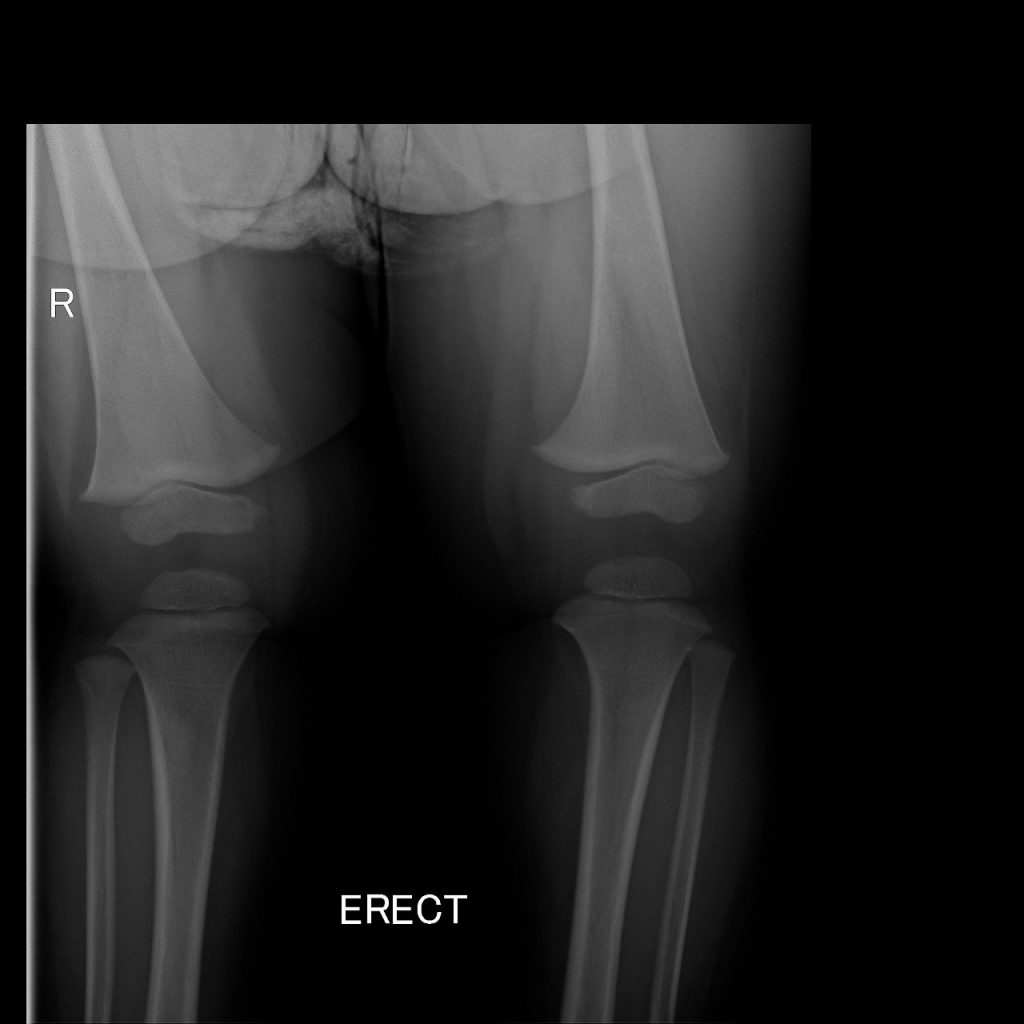

BURNT OUT RICKETS

Rickets is a disease of childhood characterized by deformities of the skeleton. It is usually the result of a vitamin D deficiency. Less commonly, it is seen as a result of a phosphate metabolic abnormality. One would not expect vitamin D deficiency in a sunny country like South Africa, but with the change of lifestyle it does become more prevalent.

These are the pre- and post-op XRs of a two-year-old with burnt out vitamin D deficient rickets.